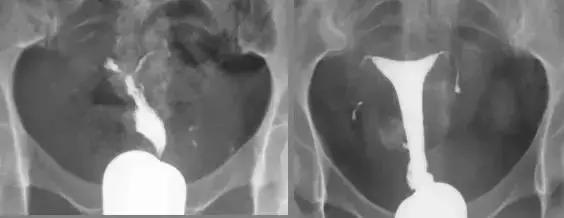

子宫结核 输卵管结核

输卵管积水